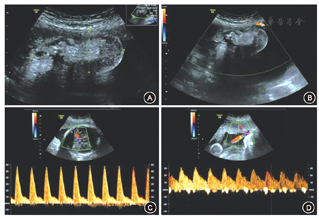

患者30岁,孕2产1,末次月经2017年7月8日。2018年4月16日,患者因"停经40周+2,阴道分泌物增多半天"入院。患者于孕11周在本院因"夫妻双方地中海贫血基因携带(女方:--SEA/αα,β-28/βN;男方:αα/αα,βIVS-2-654/βN)"行绒毛活检术,绒毛快速基因检测提示21、18、13号染色体数目均未见异常,绒毛地中海贫血基因检测提示β地中海贫血-28突变杂合子。中孕期排畸超声未发现明显异常;孕33周+超声发现胎盘胎儿面内异常回声,大小为6.9 cm×3.1 cm,以无回声为主,其内可见强回声光团;彩色多普勒血流显像未探及明显血流信号,不排除胎盘畸胎瘤可能(图1)。孕35周+盆腔MRI提示子宫底部左侧、胎盘左上缘偏内侧可见囊性不规则混杂信号影,病灶大小约4.5 cm×3.9 cm×2.7 cm,边缘清晰,边缘可见包膜,考虑畸胎瘤可能,也不排除死胎可能(图2)。2018年4月18日(孕40周+4)经阴道分娩一活女婴,出生体重3 320 g,外观未见畸形,1、5和10 min Apgar评分均为10分。胎盘于胎儿自然娩出后5 min自然完整娩出。病理检查:胎盘大小为21 cm×18 cm×2 cm,胎儿面光滑,母体面完整;在胎盘边缘的羊膜和绒毛膜之间发现1个6.5 cm×5.0 cm×3.0 cm的光滑椭圆形被覆皮肤的结节,质地中等,无蒂(图3)。剖开后切面局部可见软骨。显微镜检查可见完整皮肤结构,有表皮、真皮、皮肤附属物、脂肪组织、肌肉、软骨、骨、血管及神经组织(图4),病理诊断:(胎盘边缘)成熟型囊性畸胎瘤。患者于产后2 d出院。出院后随访1年,患者及其女一般情况良好。

胎盘畸胎瘤的产前诊断主要依靠超声[3]。据国内外文献报道,胎盘畸胎瘤多为单发,胎盘体积明显大于正常胎盘,外形多为光滑的圆形或椭圆形;肿瘤多位于胎盘的胎儿面羊膜和绒毛膜之间,与胎盘之间多通过一短蒂相连;羊膜腔内表现为团块状强回声,内部多无强血流信号。典型的畸胎瘤超声声像图特征可以表现为脂液分层征、面团征、瀑布征、垂柳征、壁立结节征、多囊征、杂乱结构征、线条征及星花征等[9]。但是超声存在一定的局限性。例如,超声的视野有限,穿透性容易受影响,且超声评估可能受到胎儿位置、孕妇肥胖、羊水过少等限制,故必要时可以考虑进行MRI检查。本例在中晚孕期超声中发现胎盘的胎儿面羊膜和绒毛膜之间存在一囊性椭圆形异常回声,并进一步行MRI辅助诊断。超声对瘤体内血管、钙化、囊性成分较敏感,而MRI对瘤体内各软组织成分组成较敏感,两者联合应用,可以较好地明确瘤体性质。另外,联合应用血清生物学标志物(如癌胚抗原、甲胎蛋白、绒毛膜促性腺激素等),能够检测体积>17 mm3的畸胎瘤,灵敏度>87%[16]。组织病理学是确诊的手段。在检索到的个案报道中,显微镜下多可发现成熟脂肪组织,往往也含有皮肤、皮肤附属物、骨、软骨、肌肉、神经组织或肠上皮细胞等。本例镜下可发现一些来自中胚层和外胚层的组织,但并未发现来自内胚层的肠腔上皮或消化腺上皮组织。这进一步说明畸胎瘤是一种来源于具有多向分化潜能的生殖细胞的肿瘤,可分化为一个或多个胚层组织。